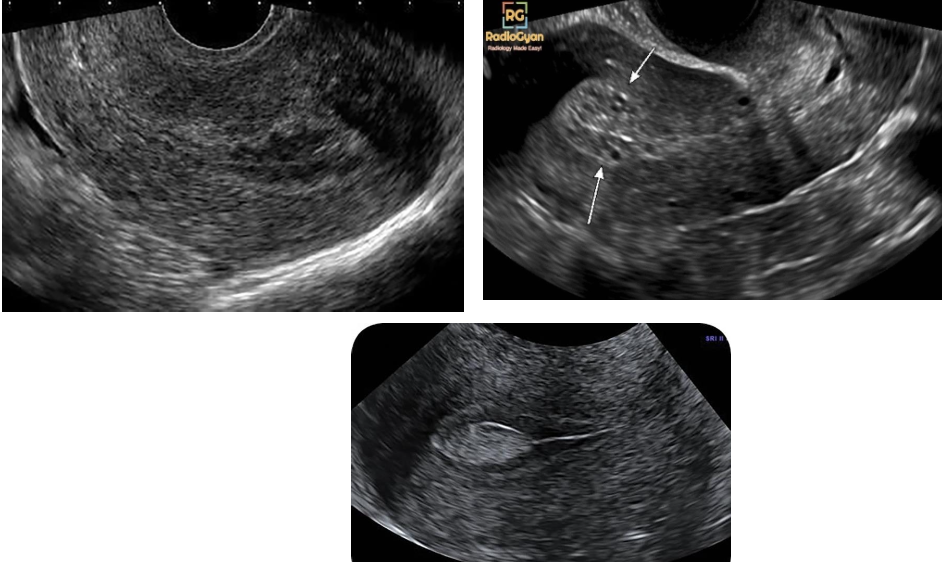

-consist of vascular plexus of arteries and veins

Sonographic findings

Sonographically, serpiginous, anechoic structures seen within the pelvis

Uterine AVMs may appear as subtle myometrial inhomogeneity, tubular spaces within myometrium,

intramural uterine mass, endometrial or cervical mass

Color Doppler diagnostic to show blood flow within anechoic structures

May be florid-colored mosaic pattern with apparent flow reversals and

areas of color aliasing

Spectral Doppler shows high-velocity, low-resistance arterial flow

coupled with high-velocity venous flow with arterial component.

Arteriovenous Malformations